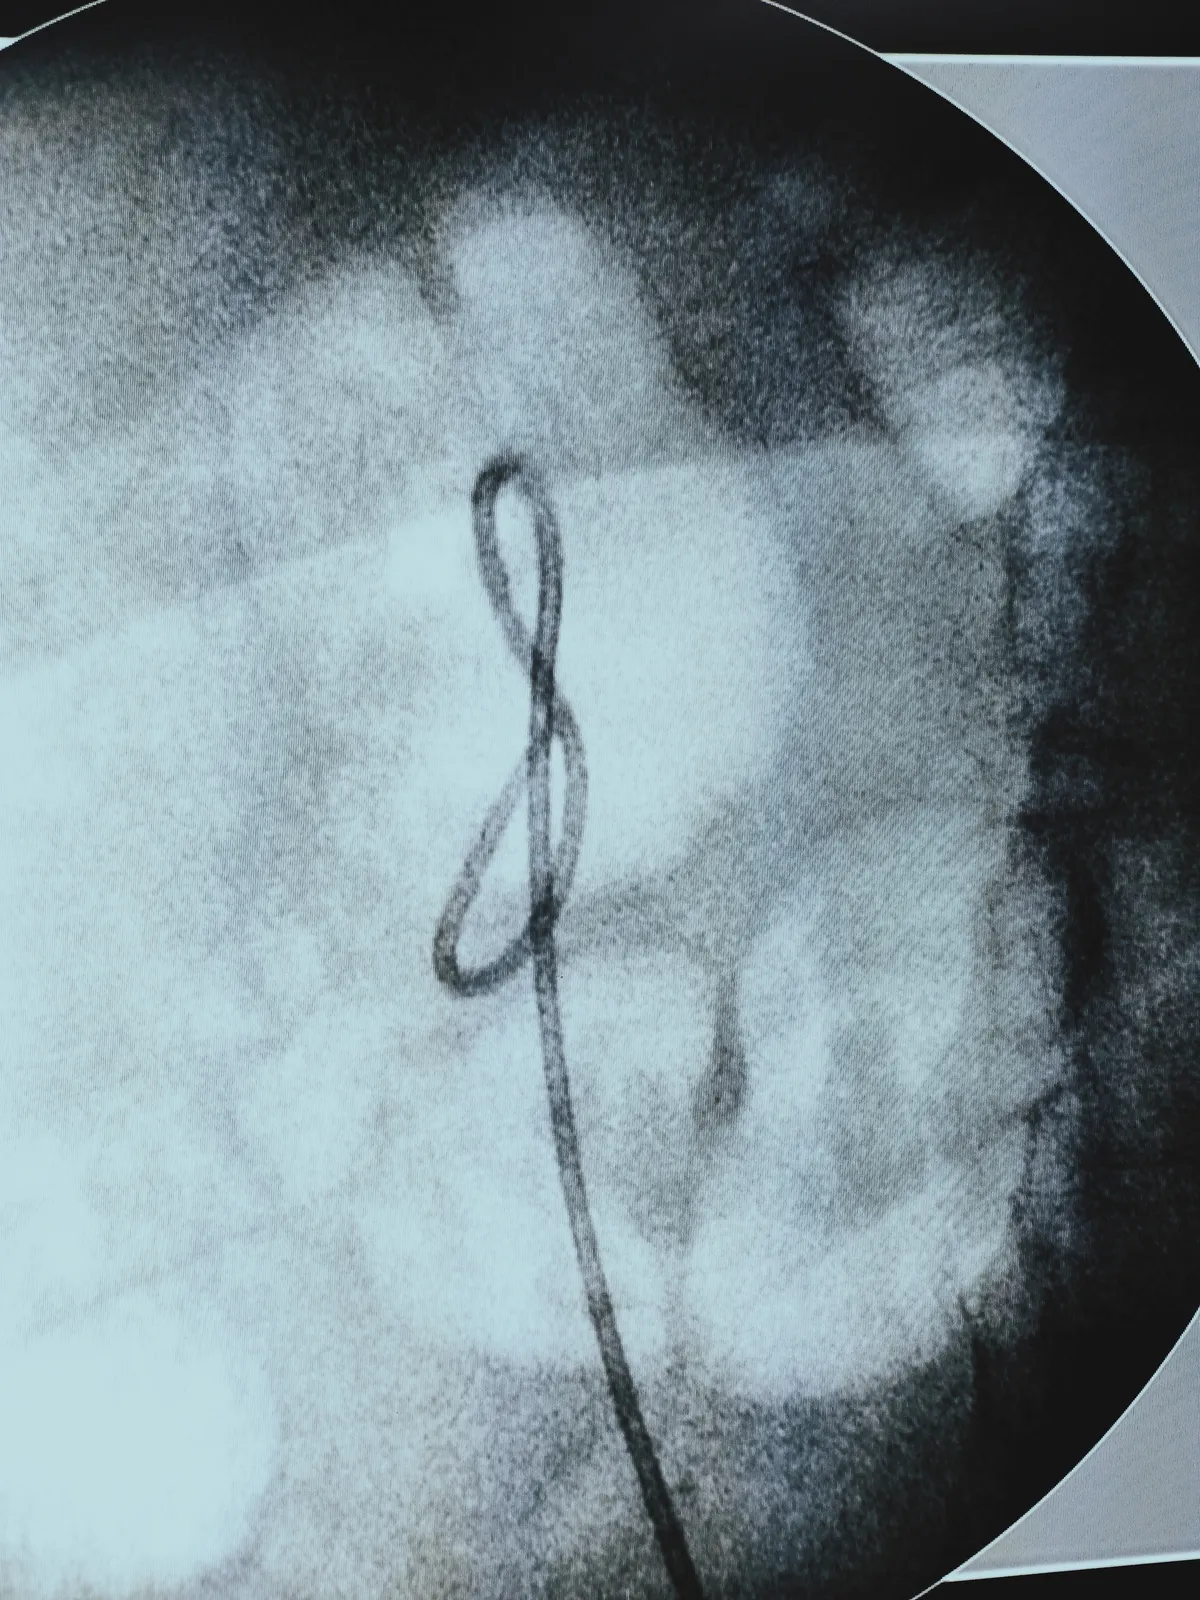

In other news, this photo sums up my passions perfectly. Medicine and music intertwined in one shot:) (this is the treble cleff sign in music)